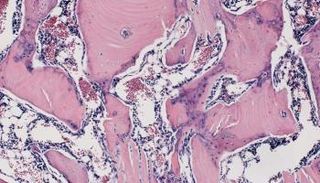

الفريق البحثي استخدم معلومة تقول إن أحد أنواع البروتينات يمكنه مساعدة خلايا جذعية على بناء عظام جديدة، وقام بتنفيذ ذلك بشكل عملي